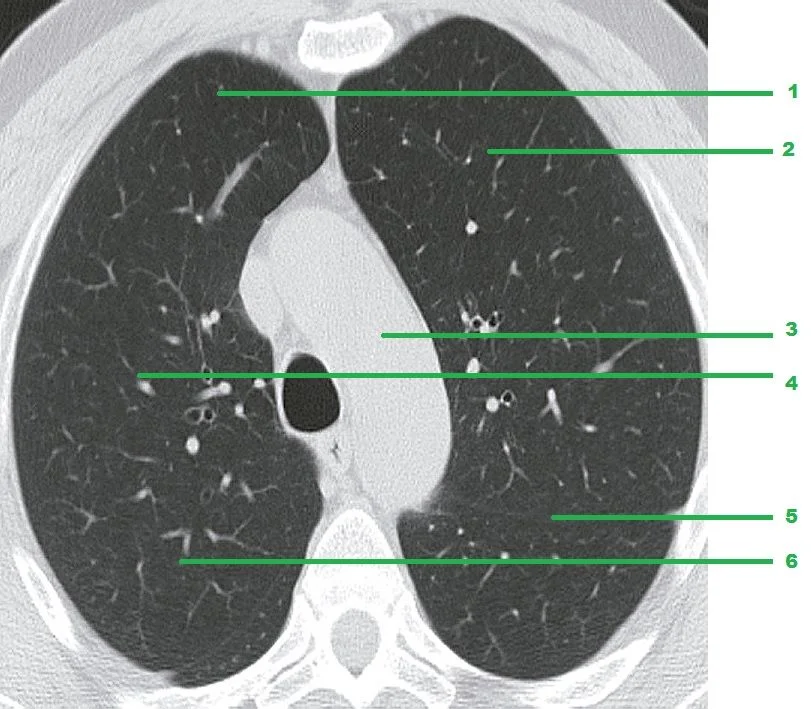

Leer másEl bronquio medio termina en la sección de TAC junto al bronquio inferior derecho que son visibles Bronquio del lóbulo

Leer másBronquio principal derecho Bronquio segmentario apical del bronquio del lóbulo superior derecho El lóbulo superior derecho bronquio surge

Leer másTraquea Bronquio principal derecho Bronquio principal izquierdo En el nivel de la quinta vértebra torácica, la tráquea se divide en

Leer másHay diez segmentos pulmonares en el pulmón derecho. El lóbulo superior del pulmón derecho comprende tres segmentos: apicales (S1), posterior